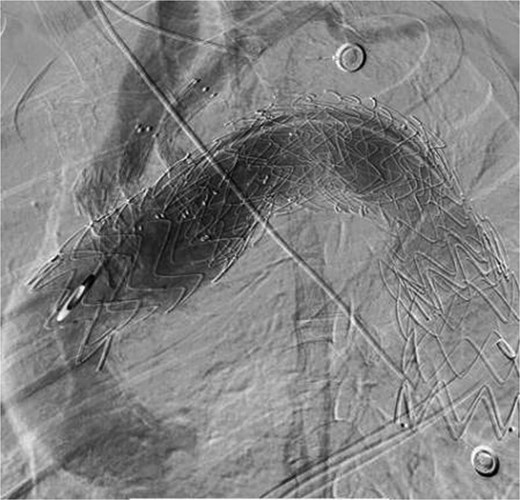

On March 1, 2024, the patient was readmitted for recurrent blood in phlegm. CTA revealed a type IV endoleak caused by membrane rupture. Angiography identified the endoleak at the stent graft junction (Fig. 8A). Controllable embolization coils were deployed to embolize the rupture. Post-surgery, symptoms disappeared (Fig. 8B).

(A) On March 1, 2024, the angiography showed endoleak (marked by arrows) at overlapping part of stent graft. (B) Dense embolization was performed on the residual breach of the stent graft membrane.